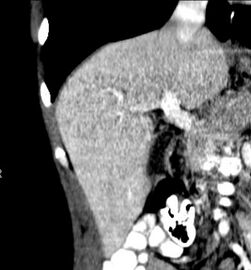

تصوير مقطعي محوسب يظهر كبد شخص بالغ في المستوى المحوري.

تحدث عملية تخلق الأعضاء من الأسبوع الثالث إلى الأسبوع الثامن أثناء عملية تكوين الأجنة البشرية. وينشأ الكبد في كل من الأديم الباطن من الأمعاء الأمامية (الأديم الباطن هو أحد الطبقات المنتشة الثلاثة للجنين) ومكونات الحاجز المستعرض المجاور للأديم الظاهر. في الجنين البشري، يكون الرتج الكبدي هو أنبوب الأديم الباطن الذي يمتد من الأمعاء الأمامية إلى الأديم الظاهر المحيط.